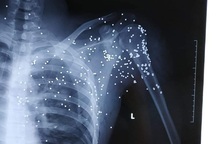

Không thấy chị H., Quý cầm súng bắn liên tục nhiều phát vào các khu vực tường trong nhà, dí súng vào đầu anh V. đe dọa. Thấy bố mẹ anh V. ra can ngăn, Quý tiếp tục chửi bới, cầm súng trên tay dí vào người các nạn nhân đe dọa. Đối tượng sau đó để lại xe ô tô, mang theo khẩu súng đi bộ về nhà.

Sau khi xảy ra vụ việc, Công an thị xã Ba Đồn đã tổ chức lực lượng tiến hành các biện pháp điều tra, nhanh chóng bắt giữ Nguyễn Đức Quý, thu giữ toàn bộ tang vật có liên quan, trong đó có khẩu súng mà Quý đã sử dụng để thực hiện hành vi của mình.